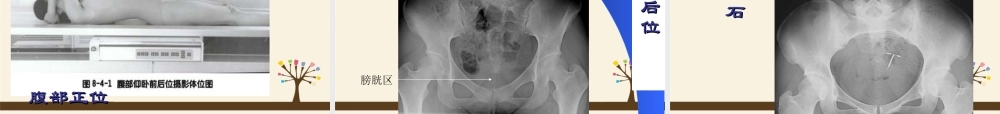

肺——后前立位【摄影体位】病人面向站立于摄影架前。人体正中矢状面与暗盒长轴中线重合,下颌略仰,暗盒上缘超出两肩。双肘屈曲,手背置于臀部,肘部尽量向前贴紧摄影架。【中心线】经肩胛骨下角连线中点(第6胸椎)垂直射人暗盒。深吸气后,屏气曝光。摄影距离为150-180cm。【用途】常规位置。胸部后前正位胸部后前正位肺——仰卧前后位【摄影体位】病人仰卧。人体正中矢状面与暗盒长轴中线重合并垂直,手背放于髂部,肘部弯曲,两肩下垂并内旋,使锁骨放平,以免遮蔽肺尖。肩胛分开,不与肺部重叠。暗盒上缘超出两肩峰3cm。【中心线】同“肺——后前立位”中心线【用途】病人站立困难或病灶靠近背部时,可用此位置。肺部仰卧前后位肺——半卧位前后位【摄影体位】采用常规“肺——仰卧前后位”体位。【中心线】采用常规“肺——仰卧前后位”中心线。【用途】病人立位困难,依靠床后靠垫。肺——侧卧后前位【摄影体位】患者侧卧于摄影台上,暗盒横放竖立,紧靠前胸,暗盒长轴中线与人体正中矢状面重合并垂直,胸部与台面中间可用棉垫垫起,以抬高胸部,使整个胸部能包括在胶片内。【中心线】采用常规“肺——仰卧前后位”中心线。【用途】用于检查少量胸腔积液,空洞的大小,少量气胸或液气胸肺——侧位【摄影体位】患者侧立于摄片架前,被检侧胸部紧靠暗盒。胸部腋中线对准暗盒中线,两臂高举,交叉放于头上,使两肩尽量不与肺野重叠。胸部长袖与暗盒长轴一致,【中心线】经肩胛骨下角,腋中线水平射人暗盒。深吸气后,屏气曝光。【用途】观察肺、纵隔、心脏、胸膜肺部侧位左肺上叶不张左肺上叶不张肺——仰卧侧位【摄影体位】患者仰卧于摄影台上,两臂高举过头,下颌稍抬高,背部可用棉垫垫高。暗盒在患侧胸部旁边竖立,与台面垂直,暗盒长轴与人体腋中线重合并垂直,并与人体正中矢状面平行,上缘约与下颌相齐。上缘包括肋弓。【中心线】同“肺——侧位”中心线【用途】检查胸内液体平面,不能采取站立肺部仰卧侧位肺——前凸位【摄影体位】患者背向摄片架站立,身体正中面或脊柱对暗盒中线。两足分开,使身体站稳。肘部弯曲,手背放于髂部.身体稍离开摄片架约30cm,上胸向后仰,使上背部紧靠暗盒,腹部向前挺出,身体冠状面与胶片成35o角。两肩尽量内旋,使肩胛骨影像不与肺部重叠。暗盒上缘须超出肩部上方约7cm。【中心线】胸骨角与剑突连线的中点,垂直射人暗盒。深吸气后,屏气曝光。【用途】肺尖病变、下胸部叶间胸膜积液及右中叶肺不张等...